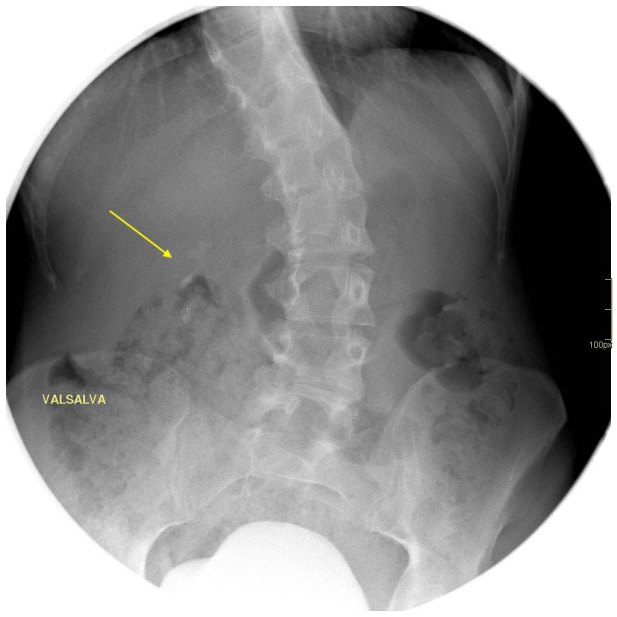

Cuando tu ves el estudio que te he enseñado, ¿Qué piensas?. Lo más normal es que pienses que el paciente, tiene una litiasis yuxtavesical izquierda, que observas en la placa simple de la imagen 2, corresponde con la imagen del TAC de Abdomen sin contraste, en la imagen 1. En el contexto de su patología, al paciente se le realiza una cistografía para valorar reflujo, que se demuestra en la imagen 3 y la imagen 4, donde puedes ver la existencia de reflujo en lado derecho, que tiñe el riñón derecho.

Finalmente, para hacerlo todo más verosímil, observas la ecografía donde ves cortes transversos y longitudinales donde ves una imagen hiperecogénica con una sombra posterior marcada, justo anclada la unión ureterovesical izquierda, al colocar el color en esa localización, podemos ver la típica imagen de artefacto de centelleo, que marca claramente la presencia de una litiasis en otros tanto estudios, imágenes 5 y 6.

Las flechas amarillas indican las regiones donde puedes encontrar la semiología que es la base del post de hoy.